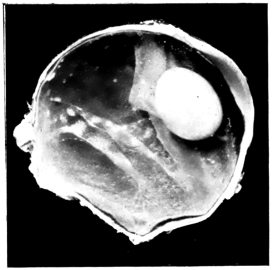

PLATE III.

16.

ABUNDANT EXUDATE INTO VITREOUS CAVITY

curly bracket span

17.

LENS FIRMLY FIXED BY ORGANIZED EXUDATE

18.

LENS FIRMLY FIXED BY ORGANIZED EXUDATE, BUT IN UNUSUAL POSITION

19.

TOTAL DETACHMENT OF RETINA, WITH CYST FORMATION

20.

RECLINED LENS LYING IN FRONT OF THE HYALOID BODY

21.

RECLINED LENS LYING IN FRONT OF THE HYALOID BODYxii